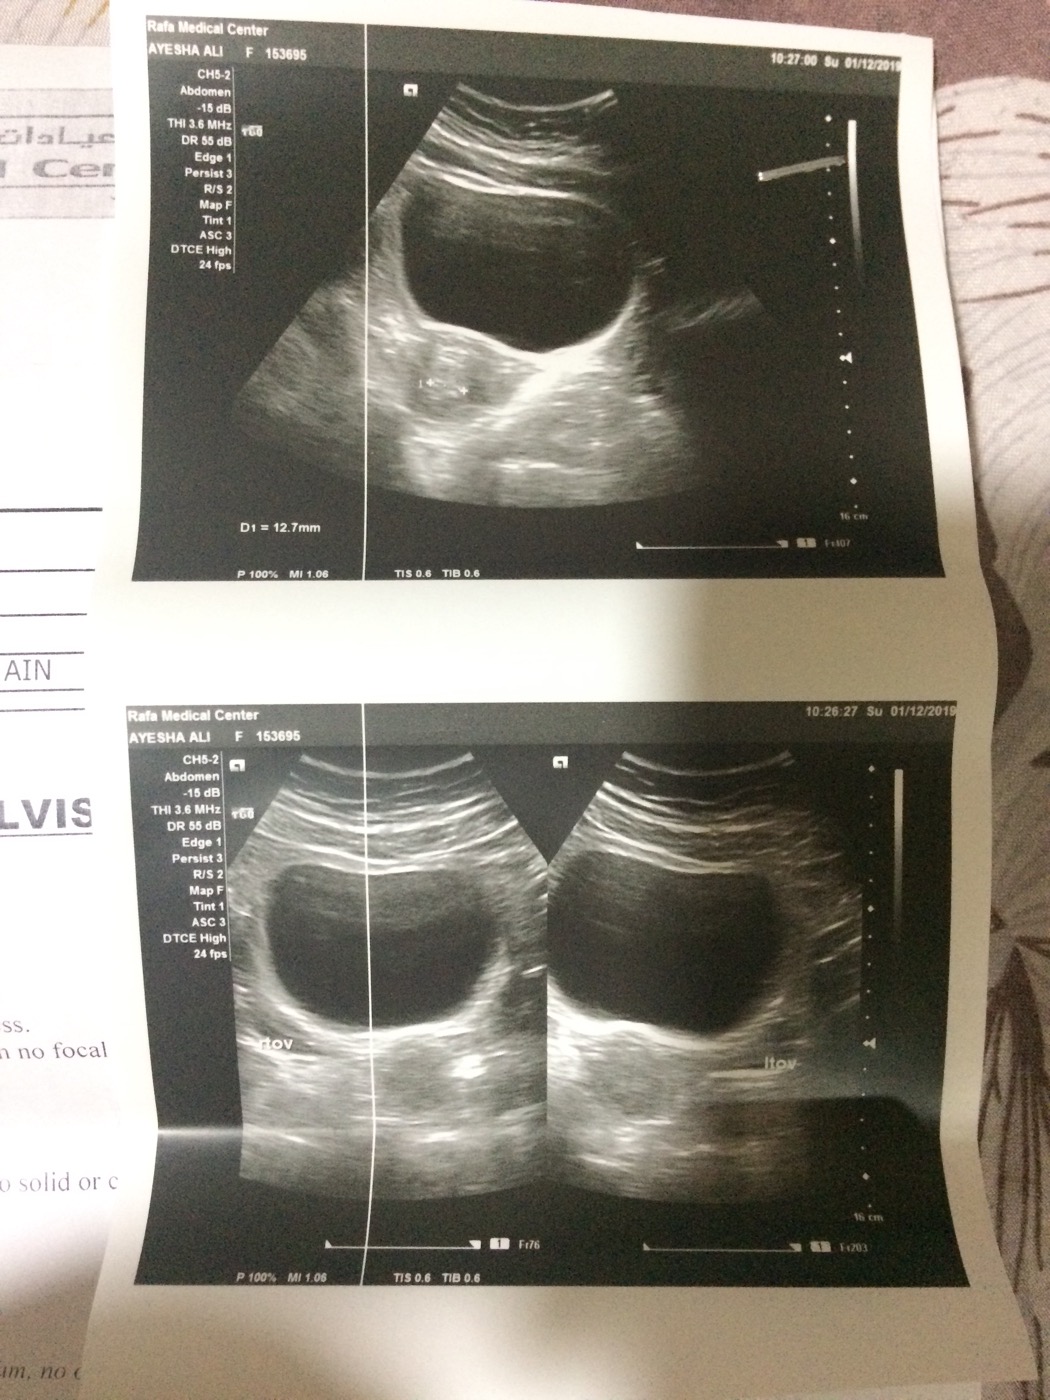

Pelvic ultrasound report is attached, kindly tell me is this suggestive of Pcos?

I had my last cycle on 15 oct after that i didn't have menses in NOV and this ultrasound was done in 1st December and pregnancy test was also negative . After that dr prescribed me duphaston for 20 days OD and said you will get menses ince med is stopped

i asked about day of cycle at which ultrasound is done cuz ur endometrial thickness is increase this is cuz u dnt have cycle last are medicine which can b prescribed only for 5 days n i will have ir imp to rule out cuz y u have irregular cycle or since how long u have history of irregular to consult properly

I am facing irregularity since last 2 months . I had 15 days late menses for the first time in oct (15 oct ) then no menses in NoV , so technically my date is 3 to 4 days a head of last month date so in that case 18 19 nov would be the day i would have menses calculating to that day ultrasound was done on 1st dec ... its on 12 day of cycle

no dear no ultrasonic evidence of PCOS is there on report

report is not suggestive of PCOS

no pco in this scan...

Normal report